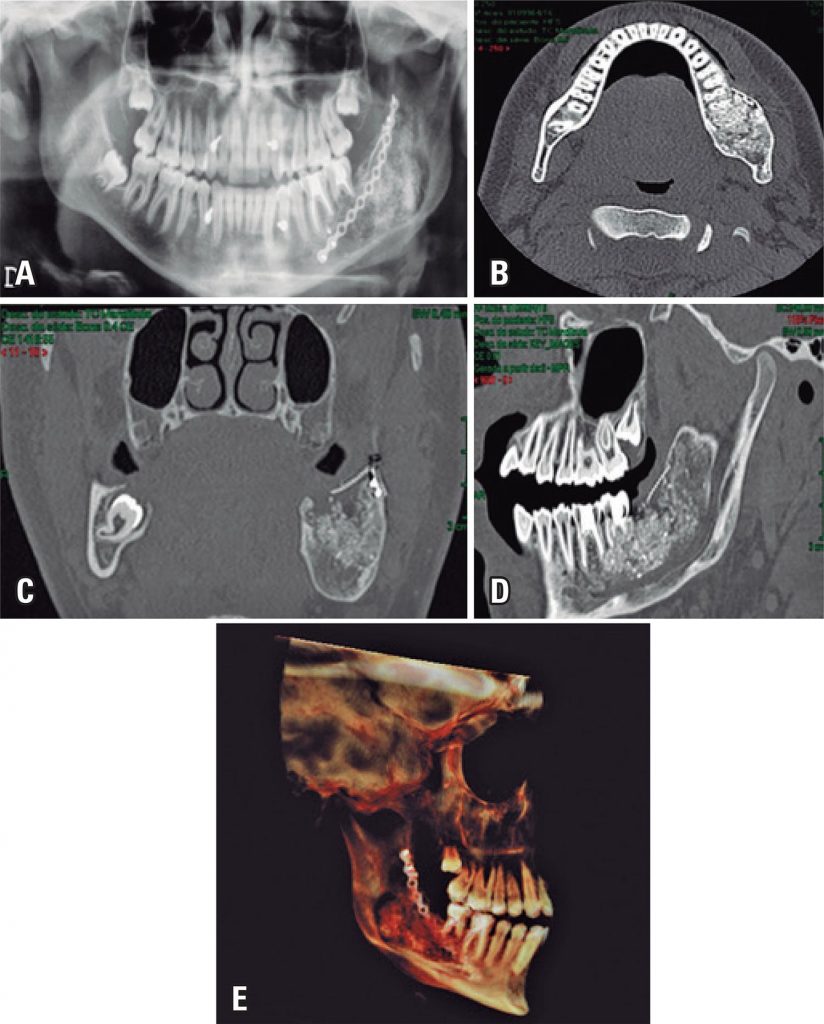

Off-label use of rhBMP-2 as bone regeneration strategies in mandibular ameloblastoma unicystic

Jawbone reconstruction after tumor resection is one of the most challenging clinical tasks for maxillofacial surgeons. Osteogenic, osteoinductive, osteoconductive and non-antigenic properties of autogenous bone place this bone as the gold standard for solving problems of bone availability. However, the need for a second surgical site to harvest the bone graft increases significantly both the cost and the morbidity associated with the reconstructive procedures. Bone grafting gained an important tool with the discovery of bone morphogenetic proteins in 1960. Benefit of obtaining functional and real bone matrix without need of second surgical site seems to be the great advantage of use bone morphogenetic proteins. This study analyzed the use of rhBMP-2 in unicystic ameloblastoma of the mandible, detailing its structure, mechanisms of cell signaling and biological efficacy, in addition to present possible advantages and disadvantages of clinical use of rhBMP-2 as bone regeneration strategy.